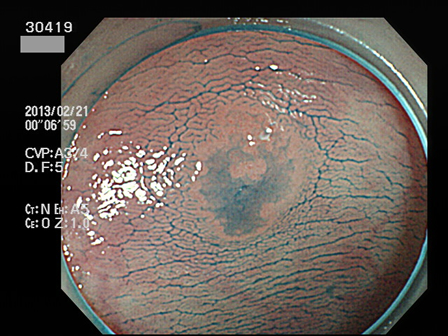

30400 30402 30405 30407 30408 30409 30413 30417 30419 30420 30422 30424 30428 30429 30432 30434 30442 30443 30444 30445 30446 30450 30451 30453 30458 30463 30464 30465 30467 30471 30472 30473 30474 30475 30476 30483 30487 30490 30492 30494 30496 30497 30499・・・・・・・の43名

上記100名より抽出した平坦・陥凹型腺腫(=癌化の危険が高いが見落としやすい病変)の内視鏡写真